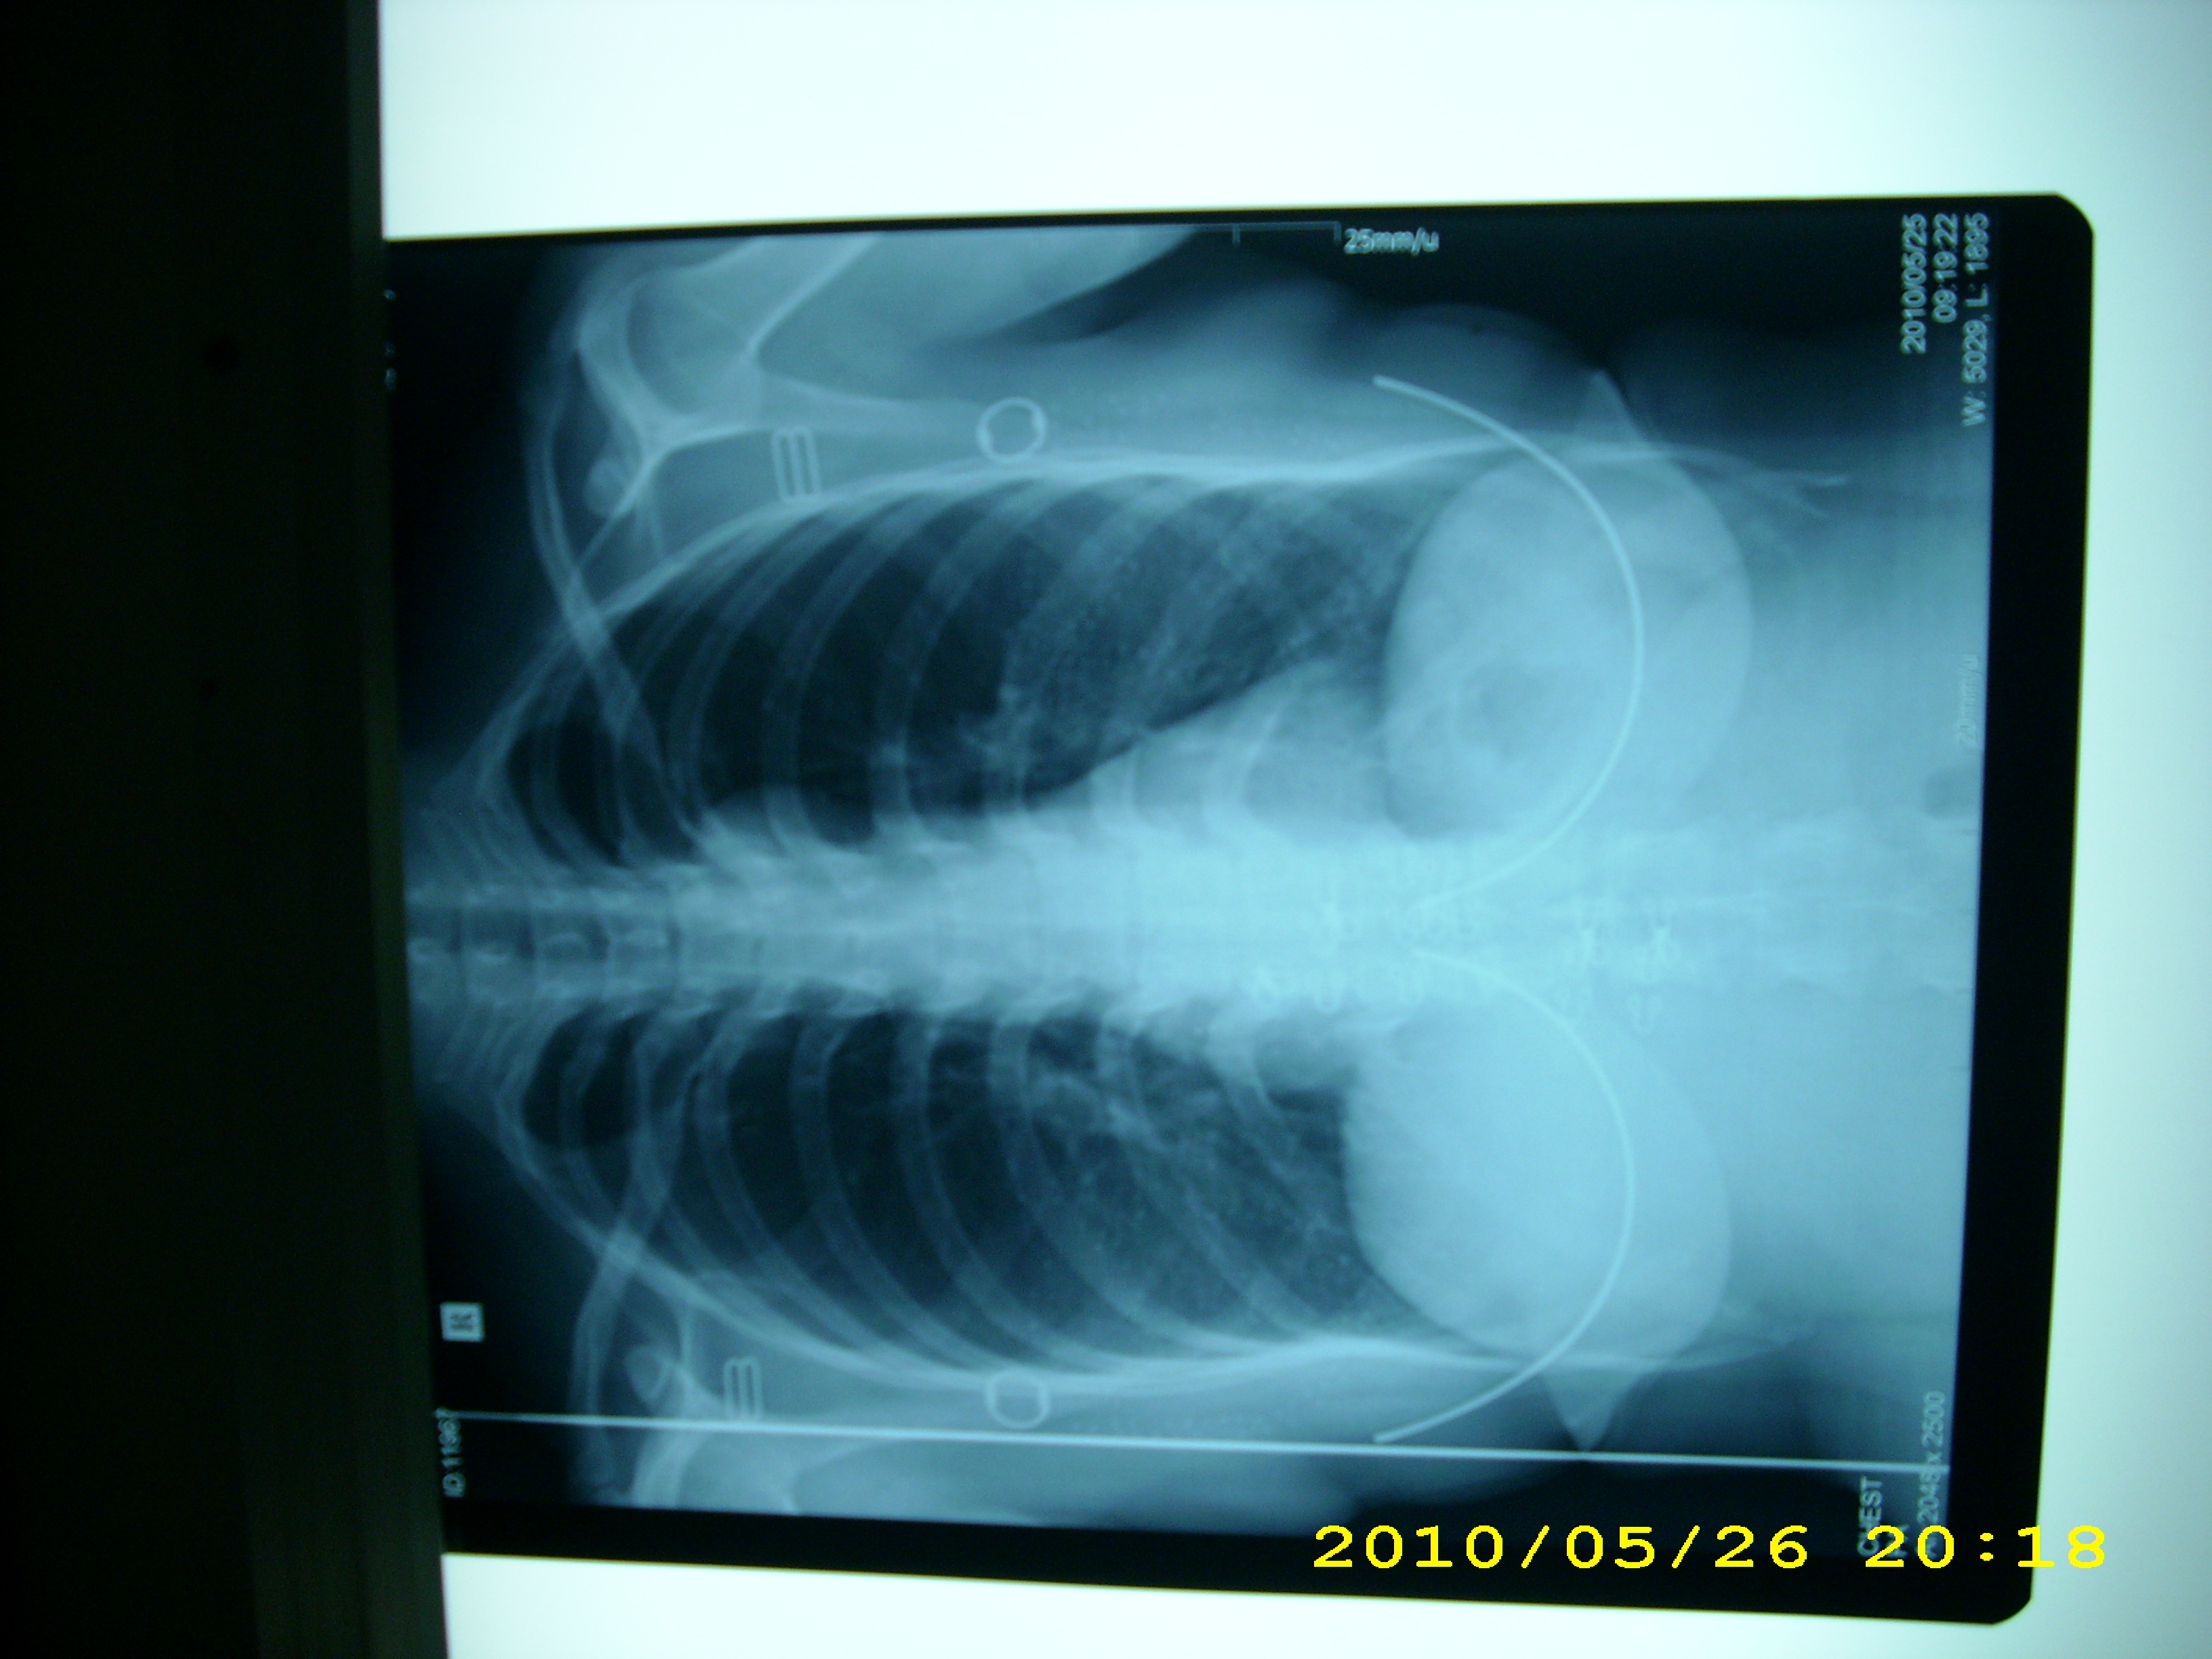

故障现象:IP板扫描后,在显示的图像上出现一条垂直走向的亮线。

(见附图)

排除过程:首先,判断问题是在光路上,分别对激光透镜,折射镜进

行检查和清洁,但是没有发现异常,亮线依旧存在。 又对PMT的激

光通道进行清洁,但也不能排除故障。 后来,从左侧向右进行检查,

发现有一个小橡胶屑位于IP板扫描缝内,正好阻挡了激光,予以清

除,故障即排除。

小结:光路有异物引起图像出现异常影像是很常见的,本例的特别之

处,就是异物的位置比较特别,应该在以后检查时注意。